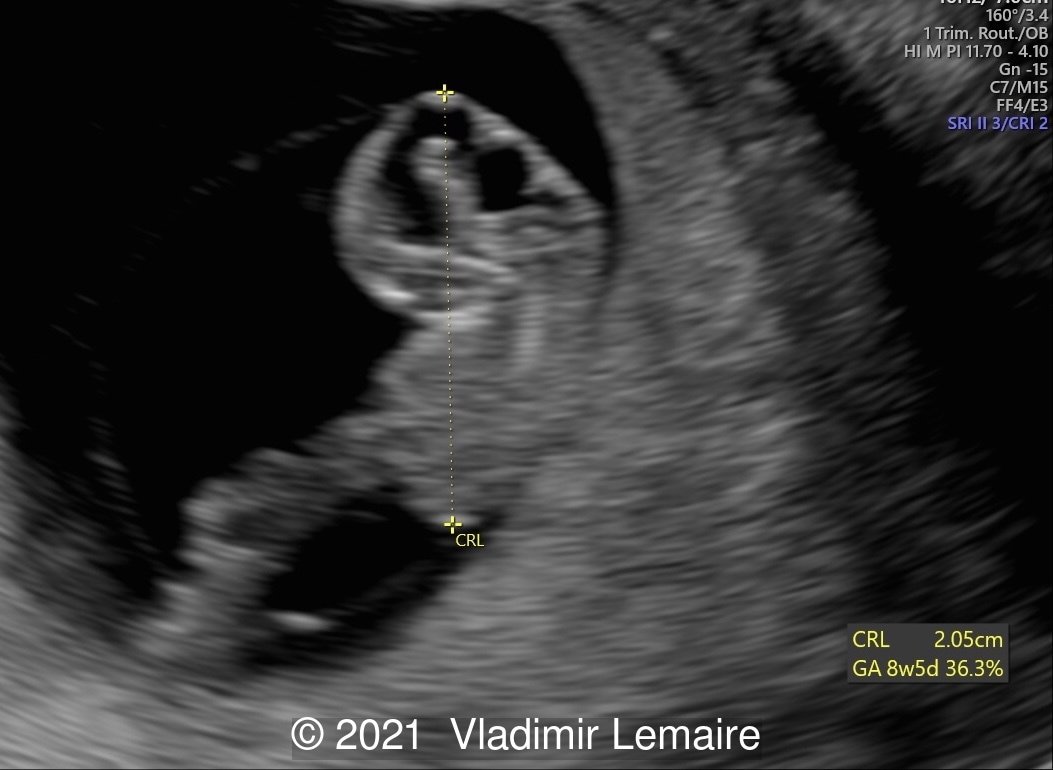

2D ultrasound showing early development of the brain.

Image 1 2D ultrasound showing early development of the brain.